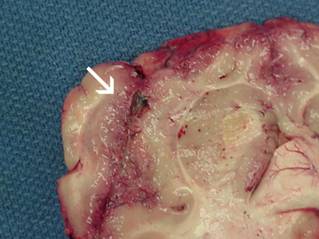

Thời kì ủ bệnh kể từ khi tiếp xúc với N. fowleri đến khi xuất hiện dấu hiệu và triệu chứng lâm sàng (thay đổi từ 2-3 ngày) trong vòng 7-15 ngày. Khi có triệu chứng, sự tiến triển bệnh rất nhanh chóng và thường gây tử vong. Khoang mũi là nơi amip N. fowleri xâm nhiễm đầu tiên. Sau khi đã bám được vào màng nhầy của mũi, N. fowleri tìm cách tiêu diệt các tế bào tại đó rồi tiếp tục xâm nhập lên não. Tại não người, N. fowleri hầu như không di chuyển tiếp tục mà tồn tại, ký sinh ở đó và chủ yếu sống bằng nguồn dinh dưỡng nhờ ăn các tế bào não.

Sau thời gian ủ bệnh, sẽ khởi phát đột ngột đau đầu hai bên trán hoặc hai bên thái dương, sốt, buồn nôn, nôn, và viêm não. Đôi khi bệnh sớm tiến triển làm thay đổi sự cảm nhận về mùi vị xảy ra là do trophozoite làm tổn thương hệ thống khứu giác. Sau đó tiến triển dẫn đến hôn mê và co giật nhanh chóng - trong khoảng thời gian 3-7 ngày. Triệu chứng gần giống như viêm màng não mủ do vi khuẩn và trong giai đoạn sớm không thể được phân biệt. Hầu hết các trường hợp sẽ dẫn đến cái chết (chiếm 98%) sau đó 1 tuần.

Do sự tiến triển bệnh vô cùng nhanh chóng, nên hiện nay phần lớn chẩn đoán lâm sàng dựa yếu tố dịch tễ (bệnh nhân gần đây có bơi trong nguồn nước ấm hay không) cùng với các triệu chứng biểu hiện. Chẩn đoán được kết luận khi trophozoite được phân lập và xác định từ dịch não tủy hoặc tế bào não. Nuôi cấy N. fowleri dễ dàng nhưng mất nhiều thời gian, còn bệnh thì tiến triển quá nhanh nên bệnh nhân sẽ có thể chết trong vòng một tuần.